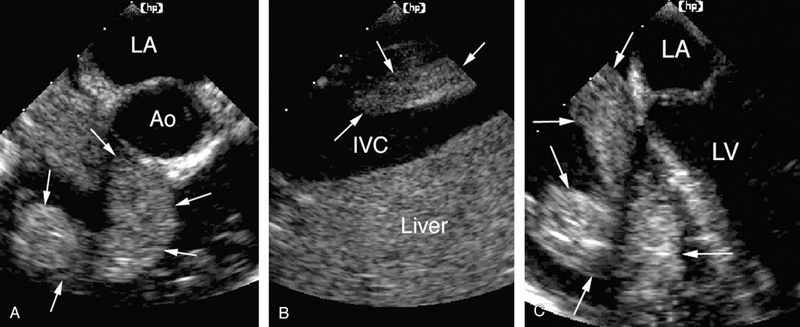

فحوصات تشخيصية لبعض امراض القلب والشرايين التاجية